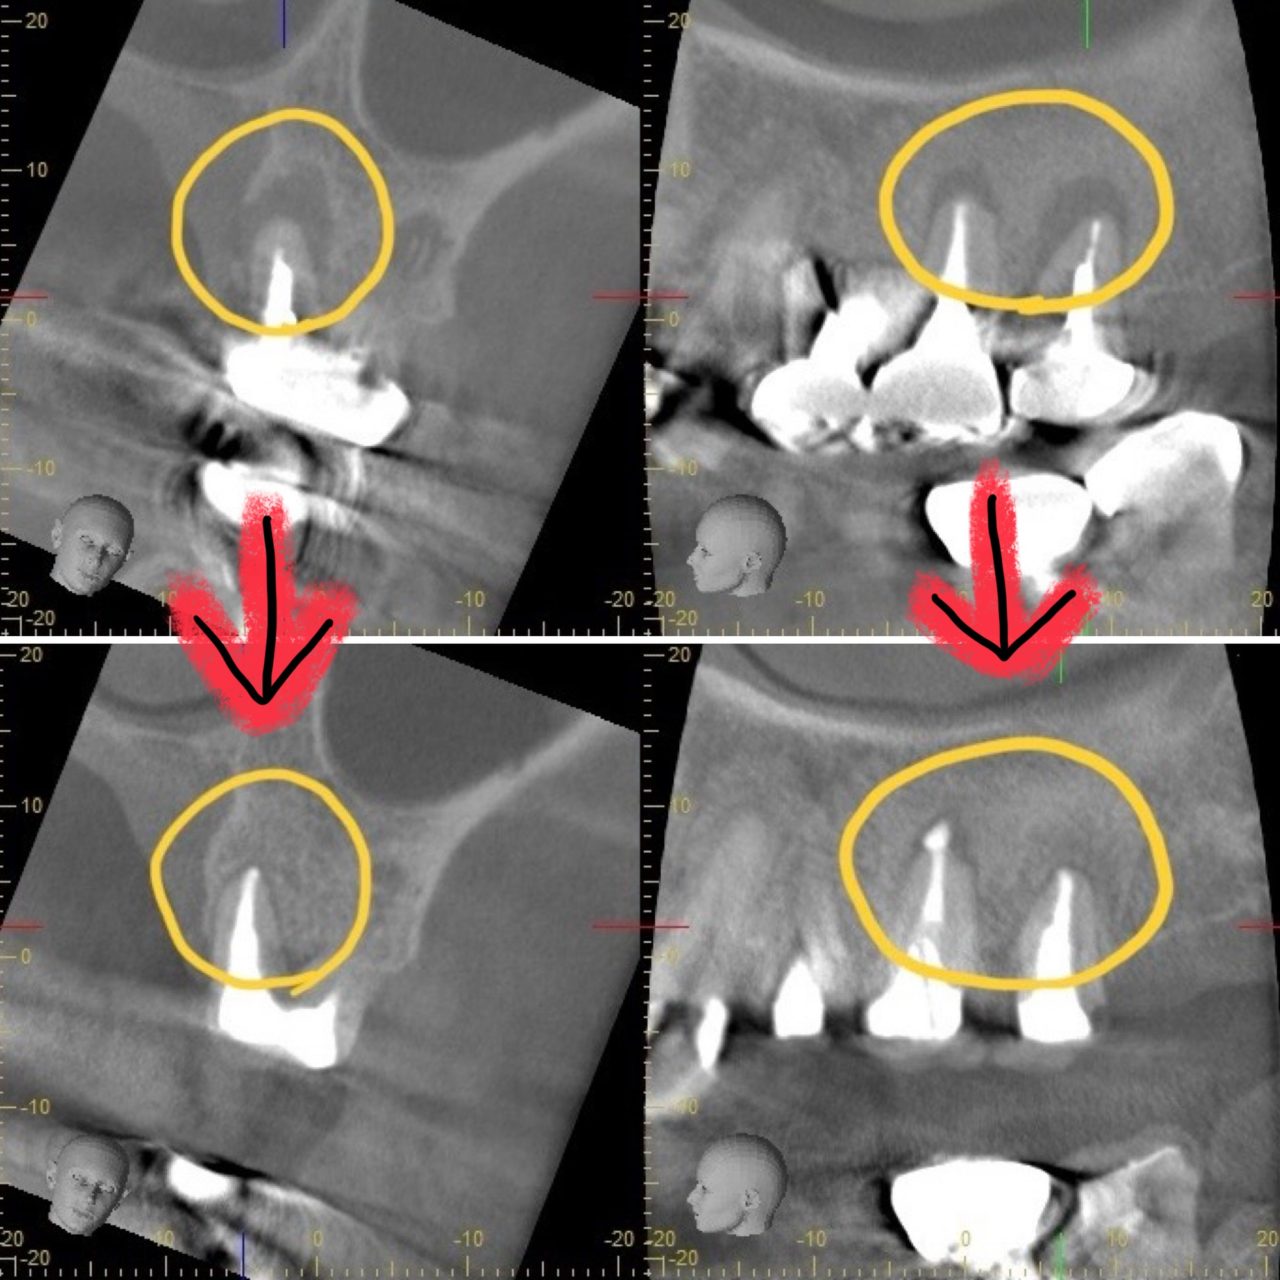

CASE2:【抜歯回避】他院で抜歯宣告された重度根尖病変の保存治療

主訴:歯が浮くような違和感(再根管治療)

歯が浮いている感じがあり、他院で抜歯と言われた

診断:CTによる精密検査で見つかった複雑な感染源

CTでしっかりと診断を行ったところ、とても深刻な状況でした。根管治療が重要ですが、それだけでは完全な治癒が望めない場合もあり、歯槽骨の再生を促す外科的処置が必要になることもあります。

こちらの患者様のように、歯槽骨のダメージが大きい症例では、根管内の感染と歯肉溝内の感染が両方の原因となっていることが多いですね。

患者様が歯を残したいという希望を叶えるために、根管治療から始めました。

根管内の感染物を取り、消毒を行なっていると、根管内から溜まった膿がドバッと出てきました。

膿がこれほど溜まっていたとすれば、患者様はかなりの痛みがあったと思います。

EDTA、次亜塩素酸、クエン酸などの消毒液を使用して、根管内を隅々まで徹底的に消毒を行い、根管内の残存歯髄も完全に取り除かなければ、二次感染のリスクが残りますので、それを十分に注意する必要があります。そこで、マイクロスコープを使用し、肉眼では見えない細かい部分まで確認しながら治療を進めました。

根尖病変によりCT上で黒く写っていた部分が白っぽくなっているのがわかりますか?

溶けていた部分の歯槽骨が回復しているということです!

また、上顎洞の肥厚は収まり、頬側の歯槽骨もくっきり映っています。予想以上に歯槽骨が回復しているので、今後外科的処置をしなくても良いのではないかと判断しました。大きなダメージがあった歯なので補綴物を入れた後も欠かさずに経過観察を行い、少しでも長くご自身の歯で生活して頂きたいと思います。